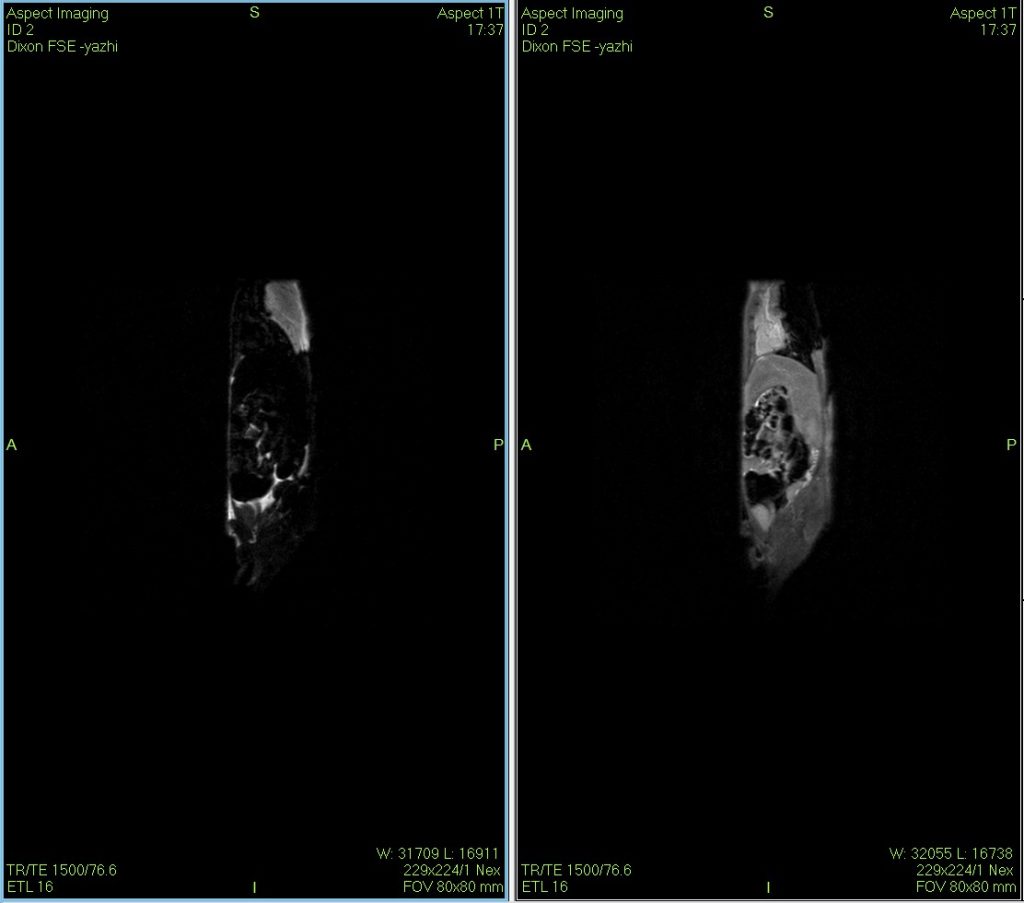

小鼠核磁共振Dixon水脂成像圖

Dixon水脂分離技術是一種使用的核磁成像技術,在某些動物疾病模型的診斷、鑒別與治療過程的評估上具有一定的獨到之處。